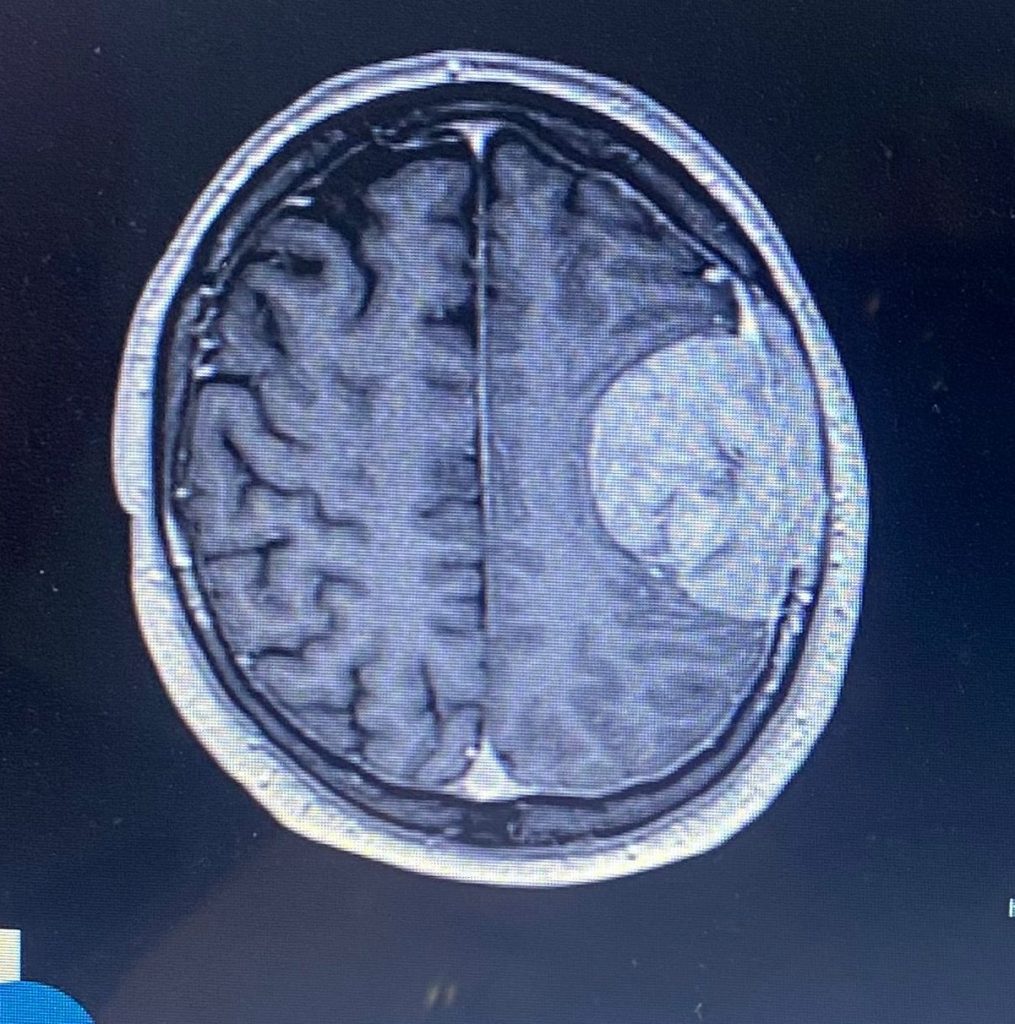

A man’s migraines turned out to be a brain tumour that was attached to his skull and now he’s unable to speak properly.

It was actually a brain tumour that was attached to his membrane and skull, which required intense removal and reconstruction.

“Around three [in the morning] they came back and said it wasn’t a stroke, but they had found a mass and that was the start of it.

And surgeons advised that because there was no evidence of cancer elsewhere, it was likely to be a slow-growing tumour that could’ve been there silently for years.

Sadly, though, it hadn’t grown into his brain and was instead attached to his membrane, as well as his skull.

He had to have the part affected removed and reconstructed using bone cement.

It was then found that he had suffered a stroke in the area responsible for speech and language.